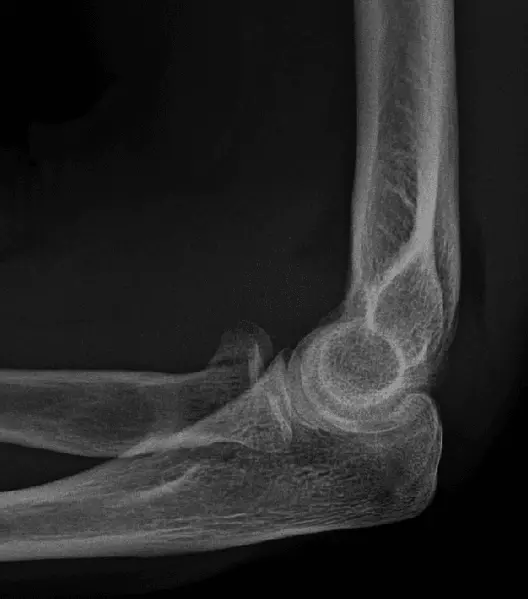

Image - X-Ray of an anterior elbow dislocation

Creative commons source by Jagadish Prabhu, Mohammed K. Faqi, Fahad AL Khalifa and Rashad K. Awad [CC BY-SA 4.0 (https://creativecommons.org/licenses/by-sa/4.0)]

This type of dislocation is where the trochlear notch is anterior to the humerus.10% of elbow dislocations are anterior dislocations, usually caused by a direct blow to the posterior elbow when it is flexed.

It presents with a popping sensation on immediate injury, pain and swelling.

A common complication of an anterior elbow dislocation is an olecranon fracture.

Treatment involves reduction, followed by a splint or a sling, and then a range of exercises for 4-6 weeks to prevent stiffness.